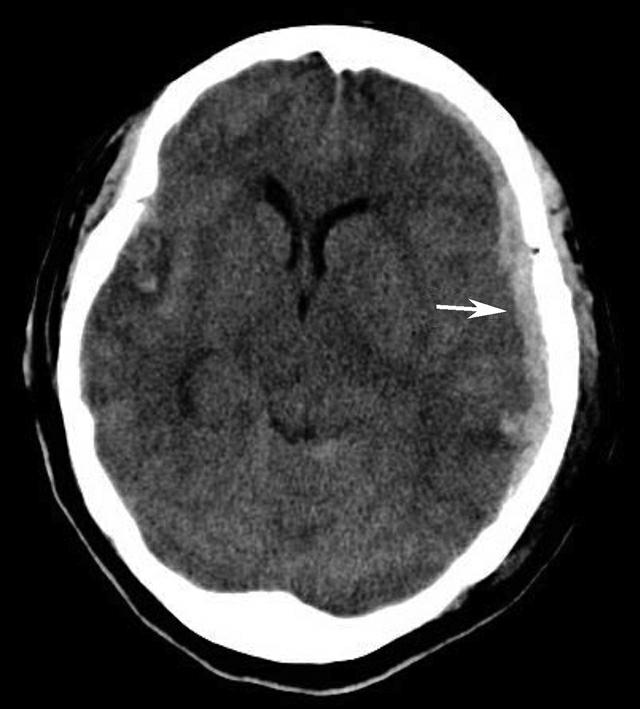

图1-2-94 蛛网膜下腔出血

双侧外侧裂池、环池、鞍上池、四叠体池、纵裂池及双侧大脑半球脑沟内示多发高密度影,CT值为72HU,双侧侧脑室后角可见高密度影